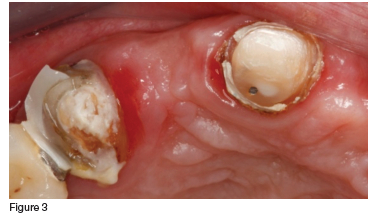

The maxilla had six remaining teeth, pain from the fractured 13 abutment tooth and grade 2 mobility of the 11 (which was expected as it had been serving as a pier abutment tooth in the provisional prosthesis (figure 3). The mandible had a severely worn acrylic hybrid prosthesis retained by five implants (figures 1 & 2).

In consultation with the patient, it was decided that, although compromised, the clinician would try to save all the maxillary teeth. Initial treatment included endodontic therapy to address the pulpitis and pain in the fractured 13, followed by crown preparations on all of the remaining maxillary teeth. These were then used as abutments for the definitive prosthesis, which was a telescopic crown-retained porcelain fused to metal fixed partial denture (figures 4, 5 & 6). The mandible was restored with an acrylic veneered implant supported hybrid prosthesis (figure 7).